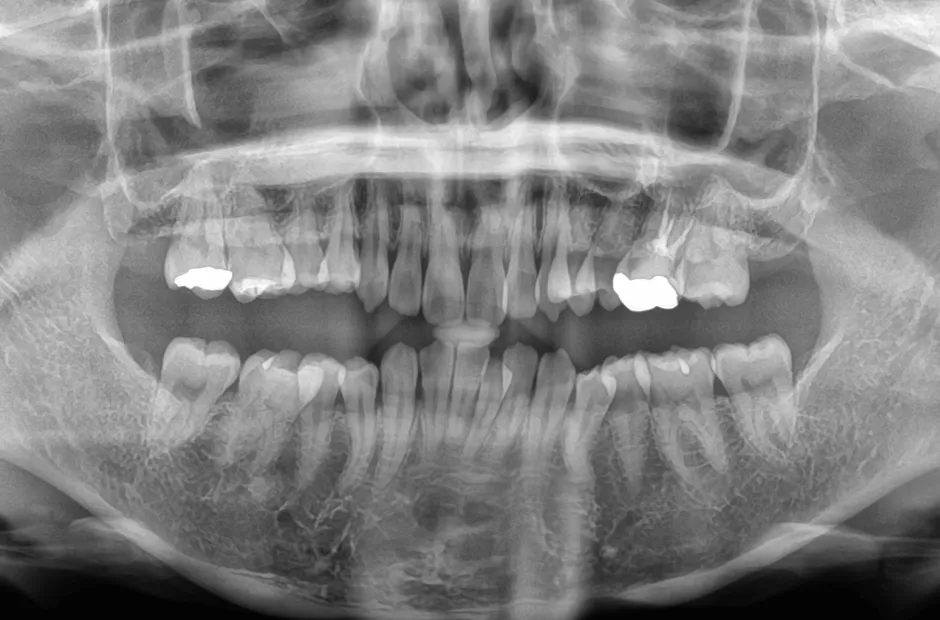

| 診断名・主訴 | 開咬 |

|---|---|

| 年齢・性別 | 23歳・女性 |

| 治療期間・回数 | 1年 12回 |

| 治療に用いた主な装置 | クワドヘリックス(QH)+タングガード → ロール付きリンガルアーチ |

| 抜歯部位 | 左右下8番 |

| 治療費 | 70万円(税抜) |

| リスク・副作用 | 装置による違和感・疼痛・歯肉退縮・歯根吸収・虫歯のリスクなど |